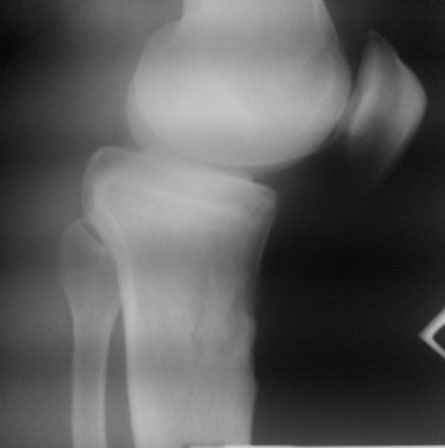

Уважаемый доктор Зайцев! Причина деформации проксимальной тибии у Вашего пациента - преждевременное и несимметричное закрытие зоны роста передней части проксимальной ростковой зоны б/б кости в следствии окультной травмы произошедшей в возрате 10-12 лет. Есть 2 причины рекурвационной деформации в области коленного сустава - мягкотканевая и костная.В данном случае Вы имеете дело не с рукурвацией коленного сустава, а с рекурвационной деформацией проксимальной голени. "Заднего выдвижного положения" на самом деле нет.То, что Вы видите на боковом снимке - это не задний подвывих голени - это снимок, сделанный в сгибании коленного сустава. Дело в том, что костные дефорсации в области коленного хорошо компенсируются за счёт движения в суставе. поэтому то, что вы видите, как задний подвывих на самом деле - сгибательное положение колена.

Это можно проверить очень просто - надо сделать стресс рентгенограмму в положении полного разгибания коленного сустава.Для этого посадите больного на стул, пятку поставьте на другой стул, дайте пациенту кассету 30Х40 держать с наружной стороны колена, и попросить ренгентехника сделать латеральный снимок с втутренней стороны. Сделав снимок здорового колена, Вы сможете расчитать деформацию.

Снимок, латеральный стресс снимок , сделанный в позиции, представленной на фотографии поможет Вам определиться в Вашей тактике и отдефференцировать суставную ( мягкотканевую) патологию от костной, или комбинированной патологии.

Ув. доктор Зайцев!

В приложении показано как делается Переразгибательный стресс снимок колена.

pdf, 76Kb

пациент наконец то объявился вновь и мы смогли выполнить новые снимки как лежа так и в нагрузке

если у вас остались силы, давайте обсудим